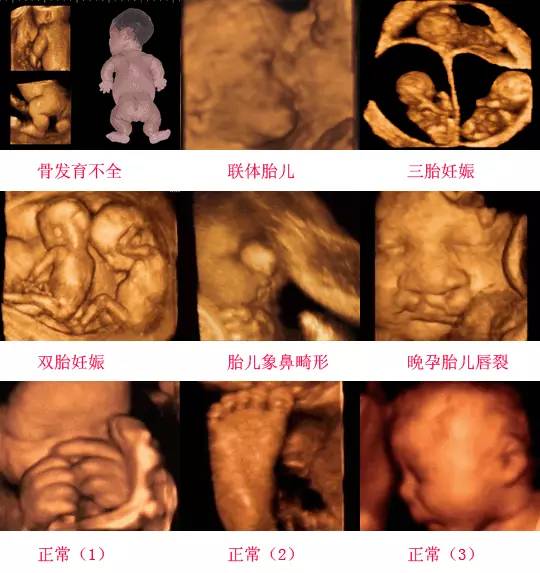

四維彩超是一種先進(jìn)的醫(yī)學(xué)影像技術(shù),通過(guò)實(shí)時(shí)觀察胎兒在母體內(nèi)的活動(dòng)情況,為醫(yī)生提供了豐富的診斷信息,在四維彩超下,我們可以清晰地觀察到胎兒的蛋蛋(睪丸)的形態(tài)、位置和大小等特征,胎兒蛋蛋是男性生殖系統(tǒng)的重要組成部分,對(duì)于胎兒的生長(zhǎng)發(fā)育具有重要意義。

在四維彩超下,胎兒蛋蛋呈現(xiàn)出特定的形態(tài)和外觀,通常情況下,胎兒蛋蛋呈現(xiàn)出圓形或橢圓形,表面光滑,內(nèi)部回聲均勻,隨著胎兒的發(fā)育,蛋蛋會(huì)逐漸增大,并呈現(xiàn)出明顯的性別特征,醫(yī)生可以通過(guò)四維彩超技術(shù),對(duì)胎兒蛋蛋的大小、形態(tài)和位置進(jìn)行評(píng)估,以判斷胎兒生殖系統(tǒng)的健康狀況。

四維彩超技術(shù)在評(píng)估胎兒蛋蛋發(fā)育方面具有重要意義,通過(guò)四維彩超,醫(yī)生可以實(shí)時(shí)觀察胎兒蛋蛋的形態(tài)、位置和大小等特征,了解胎兒生殖系統(tǒng)的發(fā)育情況,四維彩超還可以幫助醫(yī)生發(fā)現(xiàn)可能的異常情況,如睪丸未降、睪丸囊腫等,為及時(shí)采取治療措施提供依據(jù)。